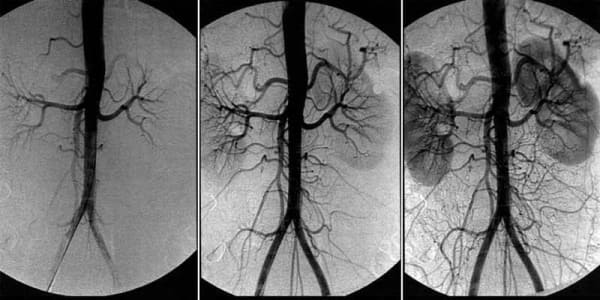

Бу "ўткир" касаллик емаслигига қарамай, миянинг қон айланишининг ёмонлашиши жуда ҳавфлидир. Охир оқибат, ертами-кечми бу инсултга олиб келади, лекин бундан олдин у одамни йиллар давомида қийноққа солади, аста-секин органлар функцияларини ўлдиради ва турли хил касалликларни келтириб чиқаради.

Ва томирларда ифлосланиш қанчалик кўп тўпланса, оқибатлари шунчалик оғир бўлади. Миянинг қон томирлари ўртача даражада ифлосланганда, кўпинча инсулт ва тўлиқ ёки қисман фалаж пайдо бўлади.

- Мия томирлари бляшка билан "тиқилиб" қолса, у камроқ озуқа олади. Ҳар йили 40 ёшдан кейин мия 5% камроқ озуқа олади.